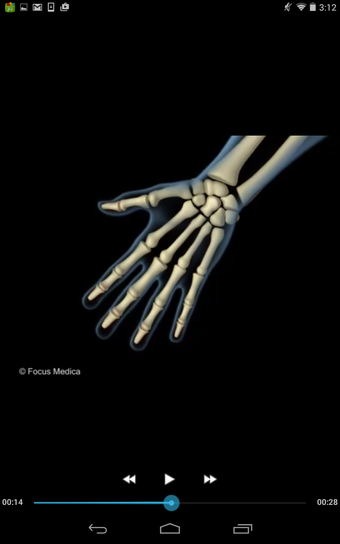

该应用程序是一本包含100个与风湿病相关的术语和定义的词典。定义以简单易用的格式呈现,辅以3D动画和视频。该应用程序分为两个部分:第一部分与医疗状况有关,第二部分与治疗和用于治疗状况的药物有关。

该应用程序是一本包含100个与风湿病相关的术语和定义的词典。定义以简单易用的格式呈现,辅以3D动画和视频。该应用程序分为两个部分:第一部分与医疗状况有关,第二部分与治疗和用于治疗状况的药物有关。